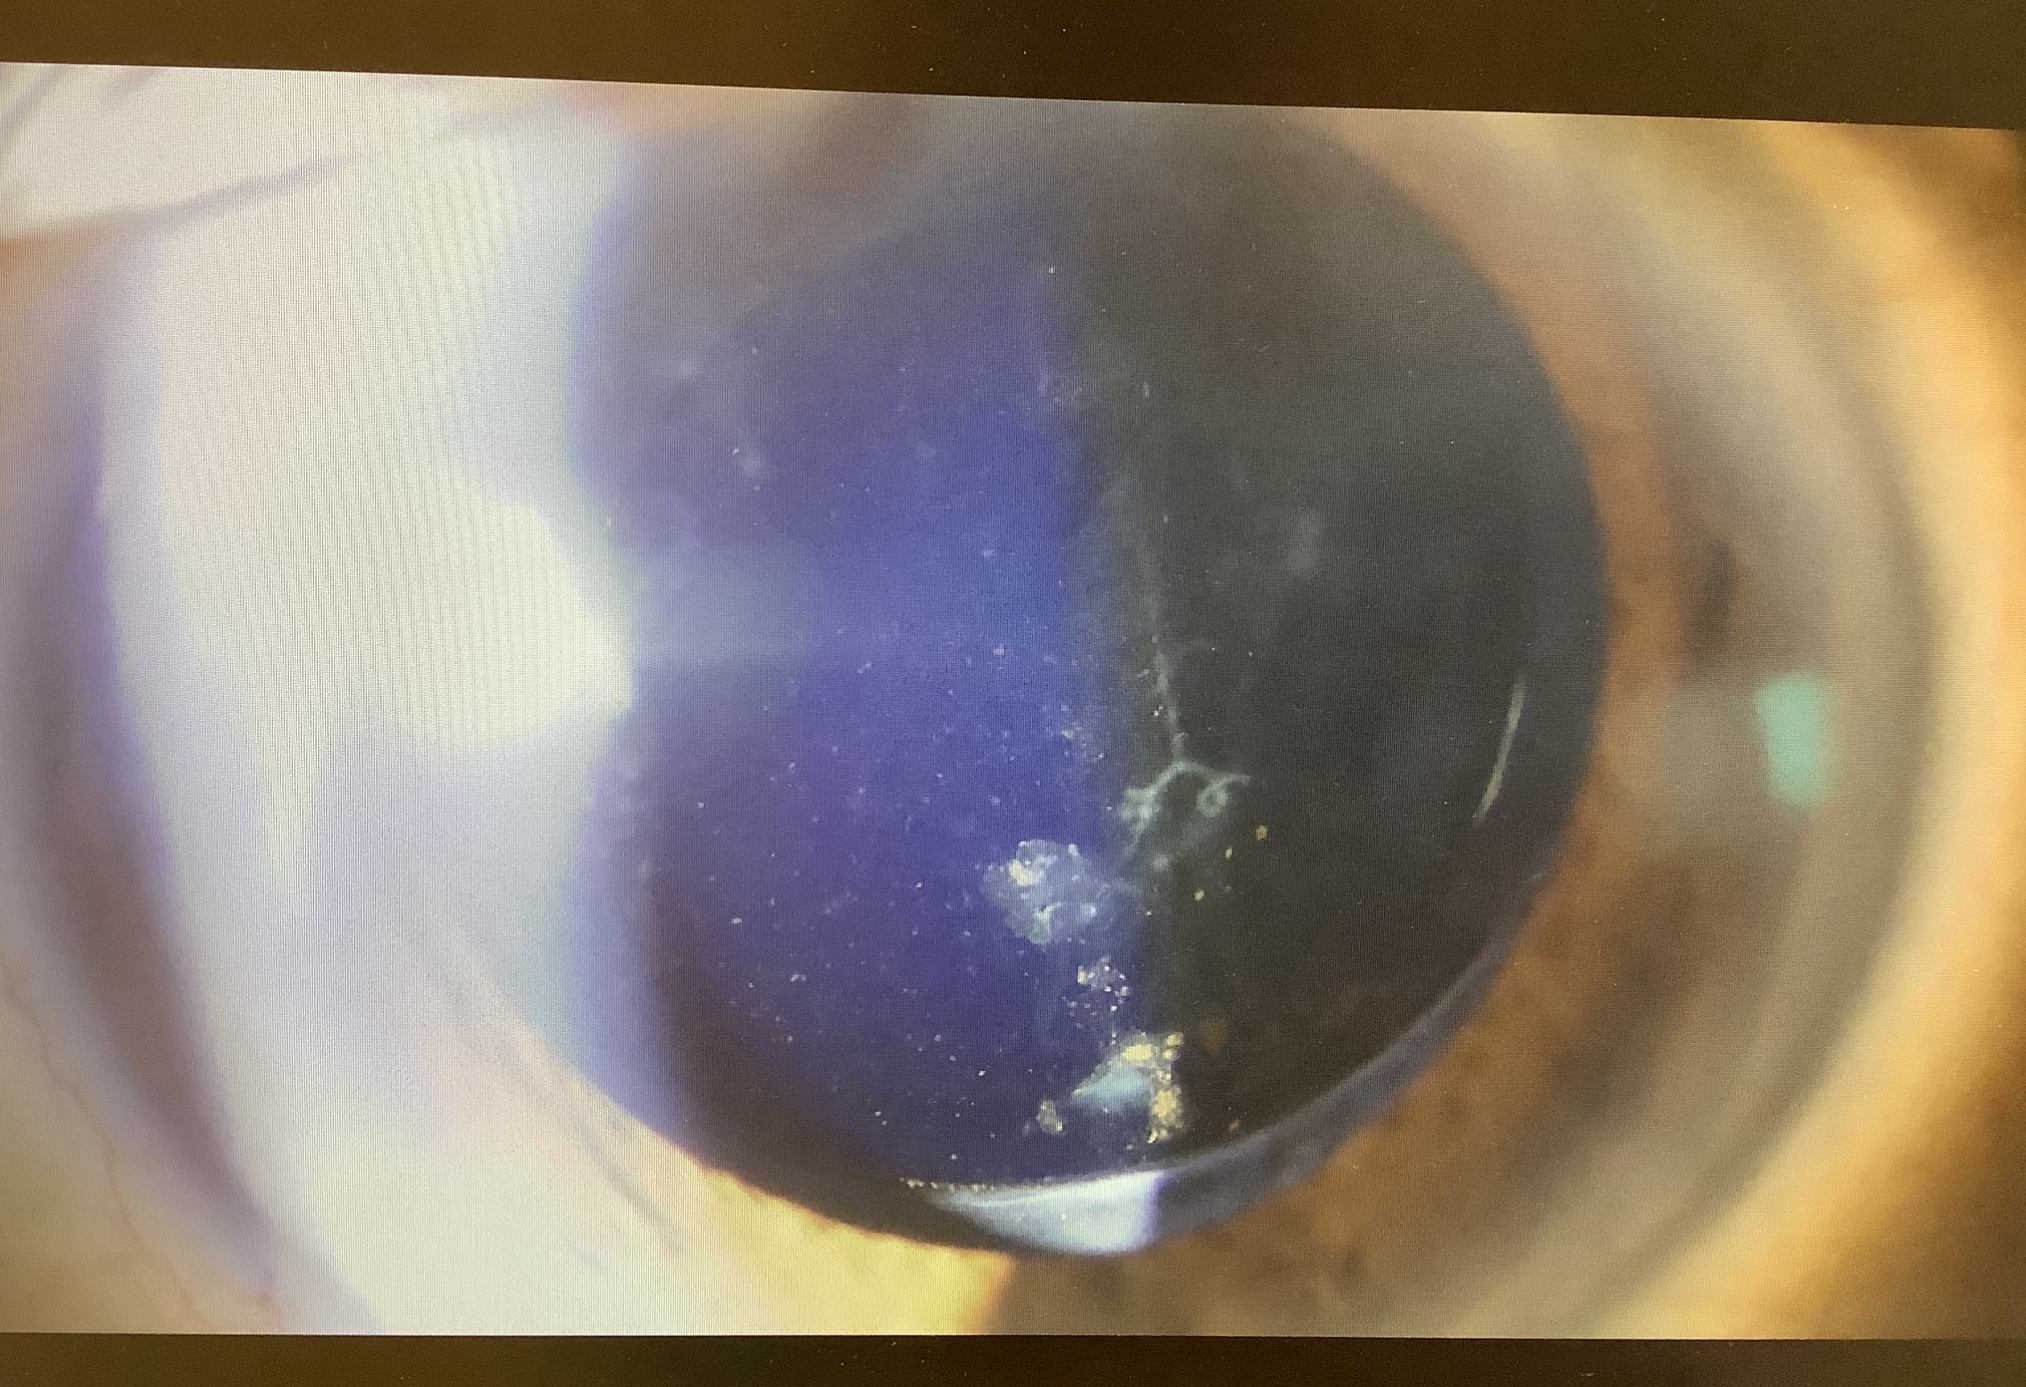

2年前の手術の時の所見では、チン小帯が弱めでCTRを入れていたので、レンズがズレて虹彩が後ろから押されて隅角が閉じて眼圧が上がったのかなと予想して、診察しましたが、レンズはきれいに入っており、グラグラ揺れる所見もありませんでした。気になるところとすれば、虹彩の色素がレンズの表面や裏側の硝子体の中に若干目立つので、色素性の眼圧上昇なのかなと思われました。